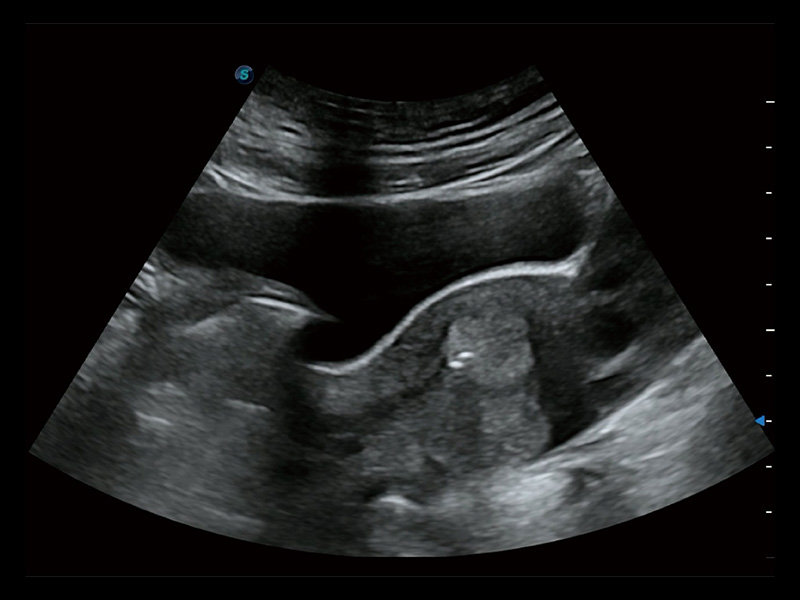

超声引导下双侧卵巢穿刺取卵

超声引导下胚胎移植